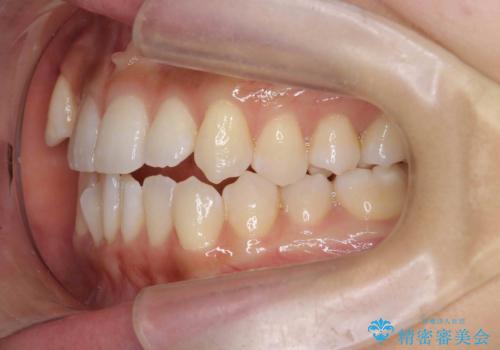

なるべく健康な歯を残したいという患者様の希望から、右側上下4番抜歯をして矯正しました。片側抜歯だったため、正中がズレないように気をつけながら治療を行いました。

正中もズレることなく主訴である八重歯と叢生を改善することができました。

患者様の満足度も高く治療を終えられました。